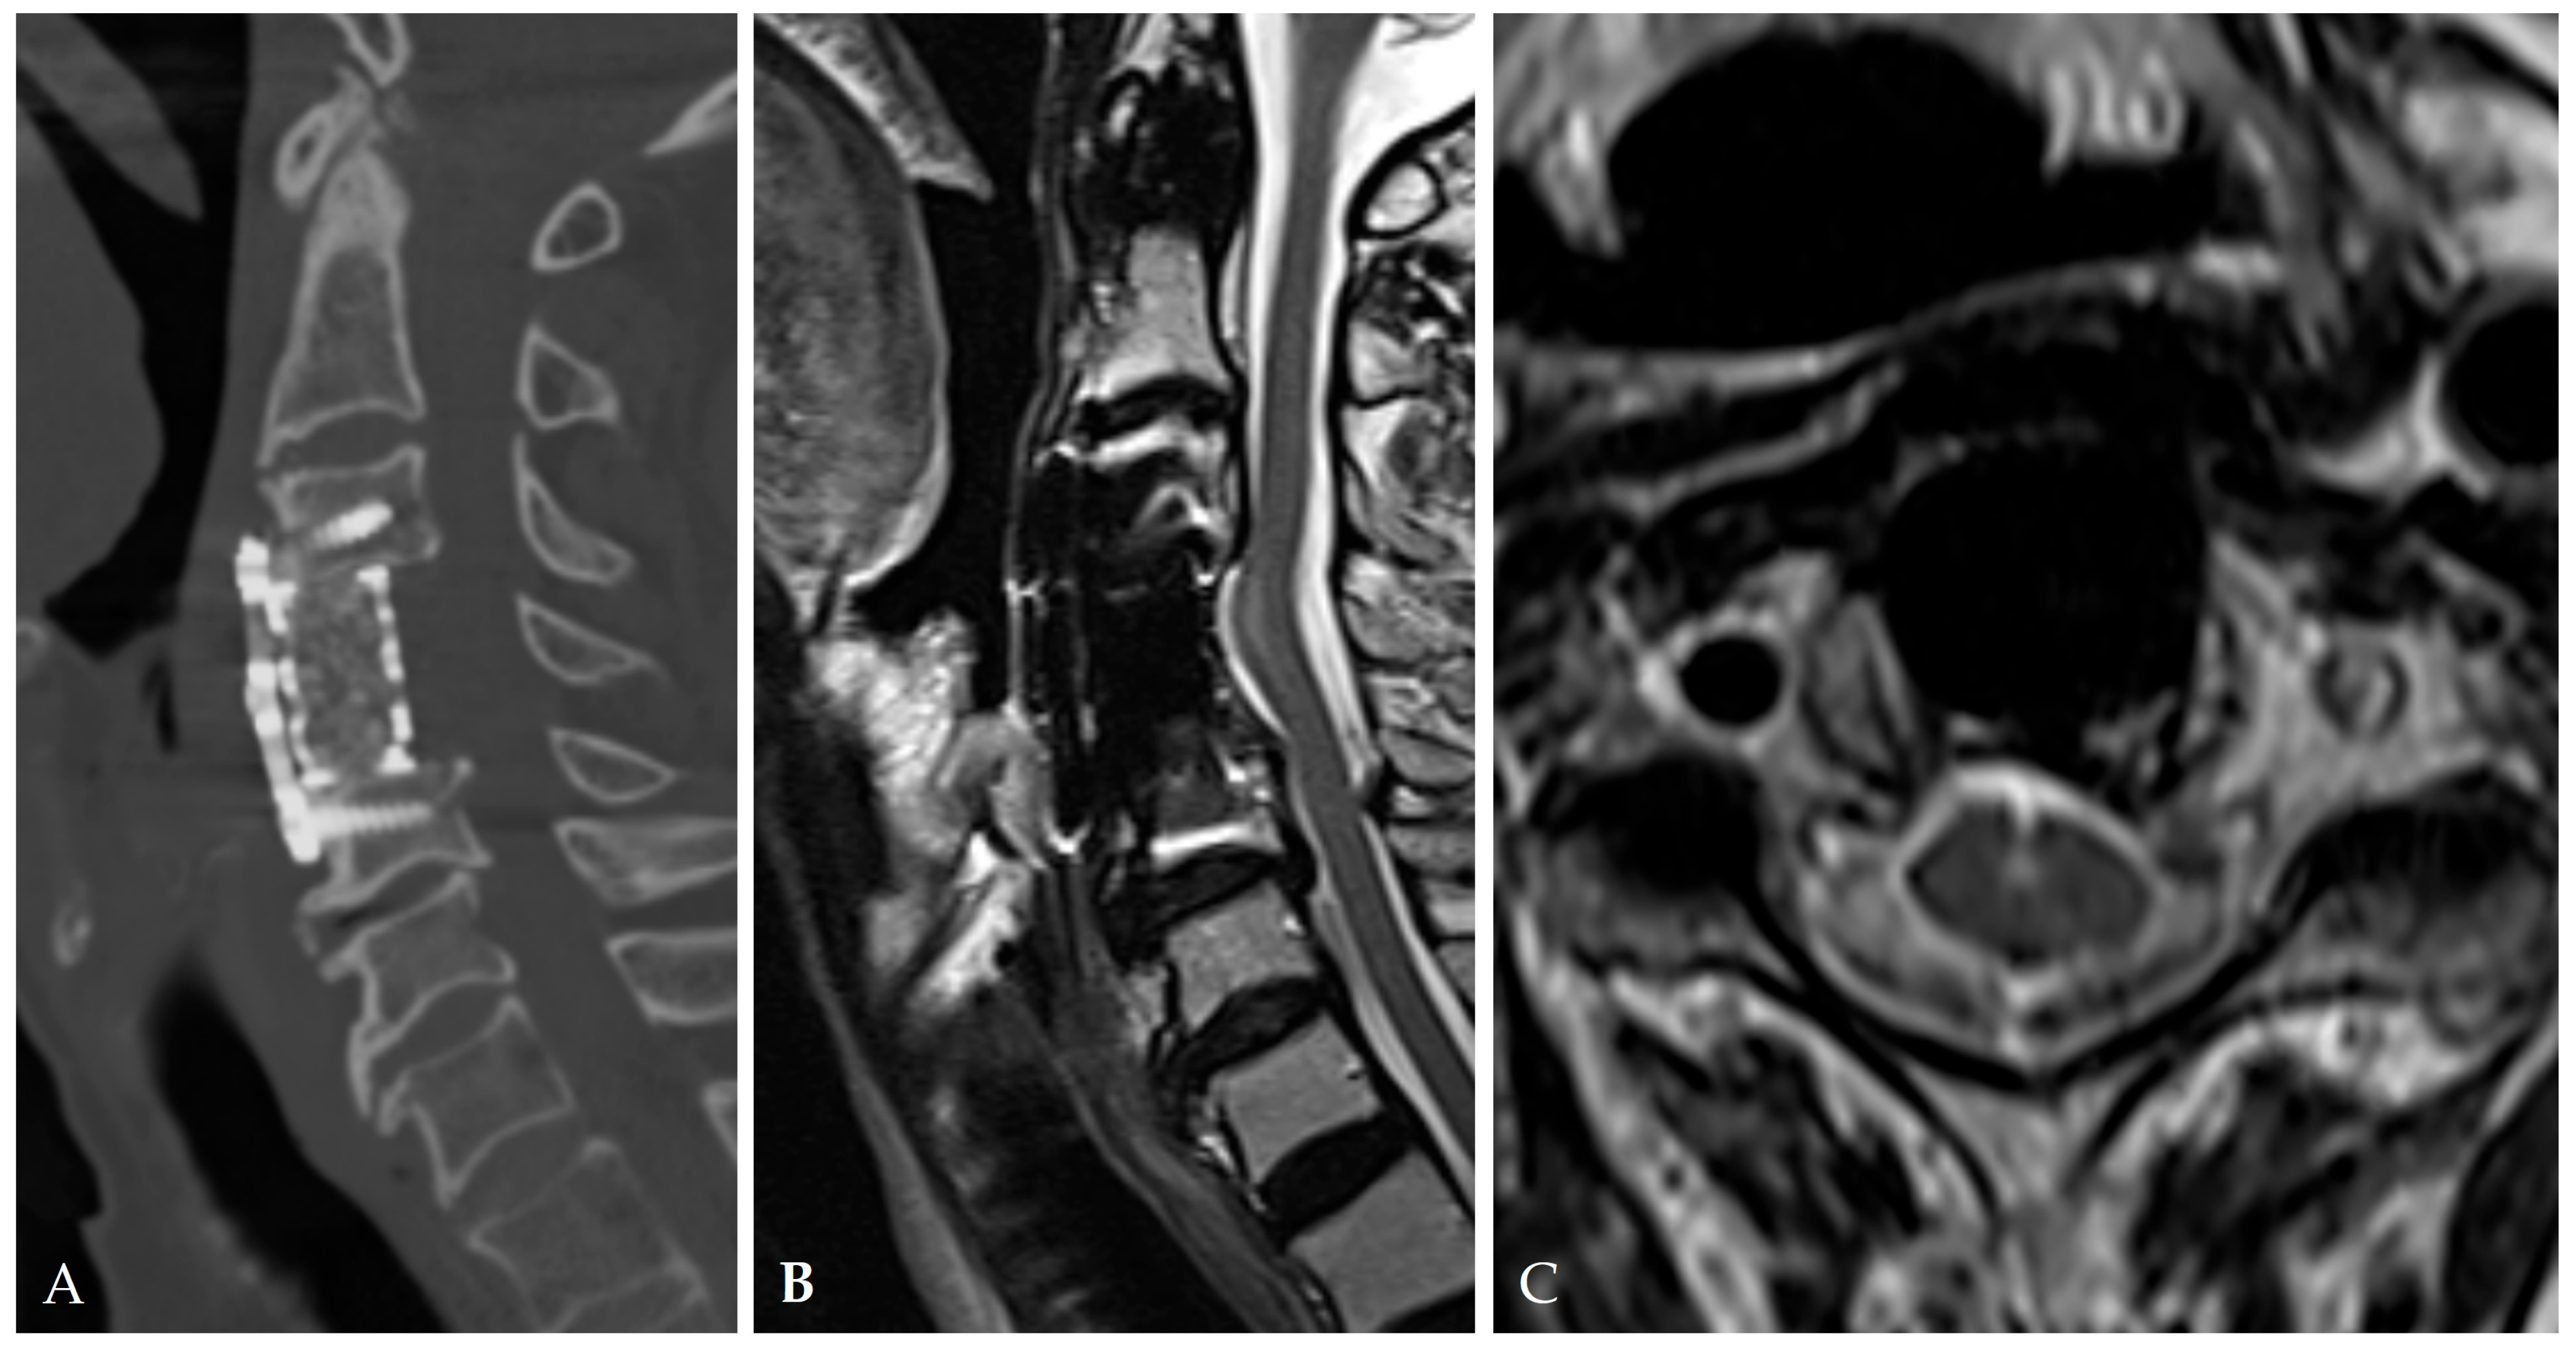

2.4. Radiologic Predictors and Morphological Correlates

2.5. Disease-Specific Factors: Dural Ossification and Adhesion Severity

3.3. Role of Dural Ossification (DO) in Leak Formation